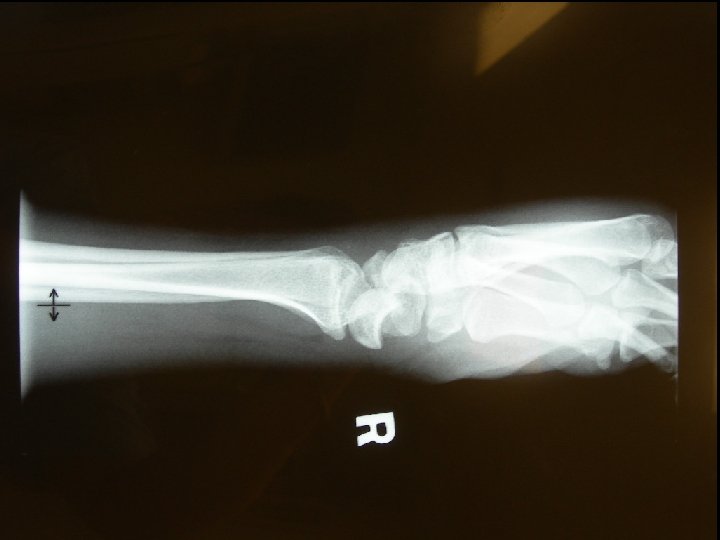

Question 2 • A 37 -year-old man attended A&E because of pain over his right wrist for one week after a fall from ladder. (a) What are the X-rays abnormalities?

Answer 2 a • Transcaphoid perilunate dislocation • Common in young adults • Fall on oustretched hand • Mechanism – bending with dorsal compression and tension on palmar surface owing to forced dorsiflexion

Perilunate Dislocation 60% with scaphoid fracture Radiolunate articulation is preserved Capitate dislocates almost always dorsal to the lunate capitolunate joint is disrupted, and the lunate projects through the space of Poirier • Proximal pole of scaphoid retains its articulation with the lunate, whereas the distal pole retains its relationship with the distal carpal row • • Image courtesy: http: //www. pt. ntu. edu. tw/hmchai/Kines 04/KINupper/Wrist. htm

Question 2 (b) What are the possible complications? • # scaphoid: – – AVN Non-union Secondary OA Sudeck atrophy • Perilunate dislocation: – – Median nerve palsy (carpal tunnel syndrome) Sudeck atrophy AVN Long-term carpal instability: Dorsal/Volar Intercalated Segment Instability (DISI/VISI) (c) What is your treatment? – Prompt ORIF